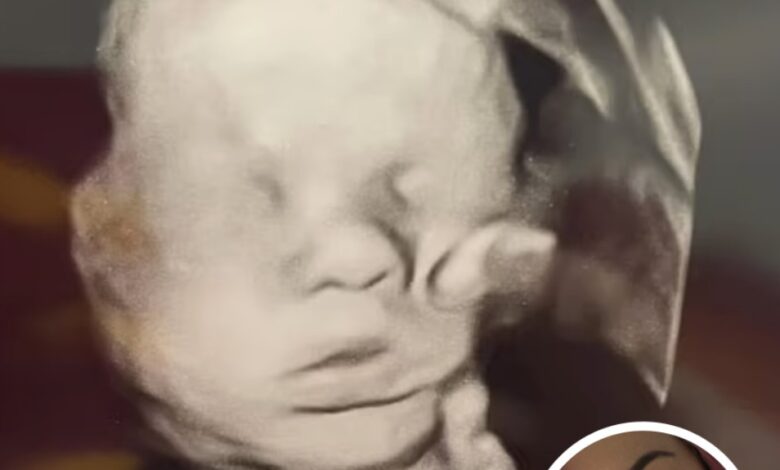

Then came the 32-week ultrasound—an appointment Amanda will never forget.

As she and her daughter Bailey sat in the dimly lit room, the screen flickered with grainy black-and-white images of her growing baby. And there, clear enough to take her breath away, appeared the shape of a large hand gently resting on her baby’s head.

Bailey was the first to notice. “Mom, look at the hand!” she exclaimed. Amanda’s heart skipped. She stared at the screen, tears welling up as a rush of gratitude and awe overwhelmed her.

To Amanda, this wasn’t just an ultrasound artifact. It was an answered prayer—a visible sign of divine protection over the child she had so desperately begged God to keep safe.

She shared the image on social media, where it quickly went viral. Thousands of viewers debated what they were seeing. Many believers called it miraculous, a message from above, a blessing captured in real time. Skeptics offered another explanation, suggesting that the “hand” was simply the baby’s own limb, distorted by the ultrasound technology.